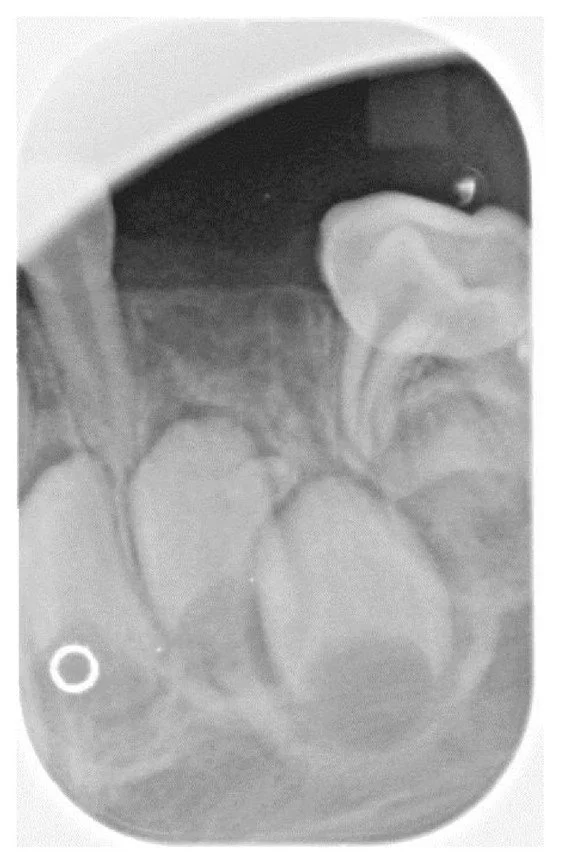

Upon evaluation, it was noted that the patient was missing the maxillary and mandibular right and left primary canines (Figure 1). Following the clinical evaluation, two bitewings in addition to maxillary and mandibular anterior periapical radiographs were obtained to evaluate proximal tooth surfaces for caries, investigate canine areas, and rule out other pathology.

Figure 1

An intraoral photo of the 4-year-old male patient shows the missing maxillary and mandibular right and left primary canines.